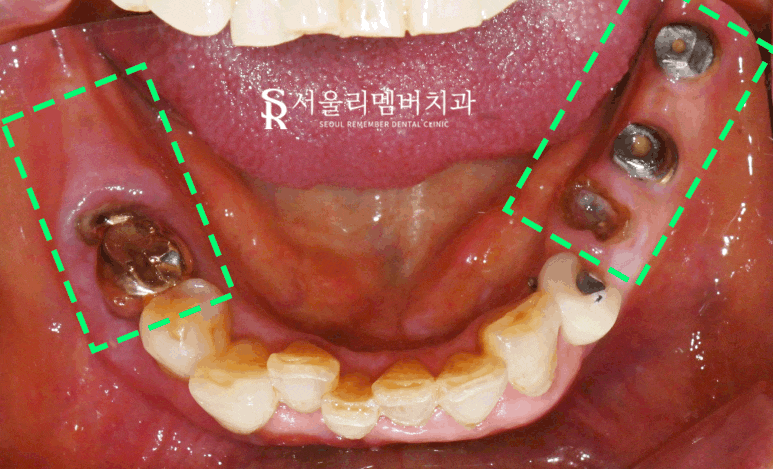

구내사진

촬영일:2024.07.10

하악도 보겠습니다.

35번은 치관이 아예 날아간 모습이며

46번 역시 뿌리만 살짝 남은 것을 볼 수 있습니다.

더불어, 양쪽 어금니는 소실되어

저작 기능 역할을 하지 못하고 있습니다.

상하악 모두 치석과 치태가

쌓여있고 이에 따라 치주 상태가

좋지 않아 보입니다.